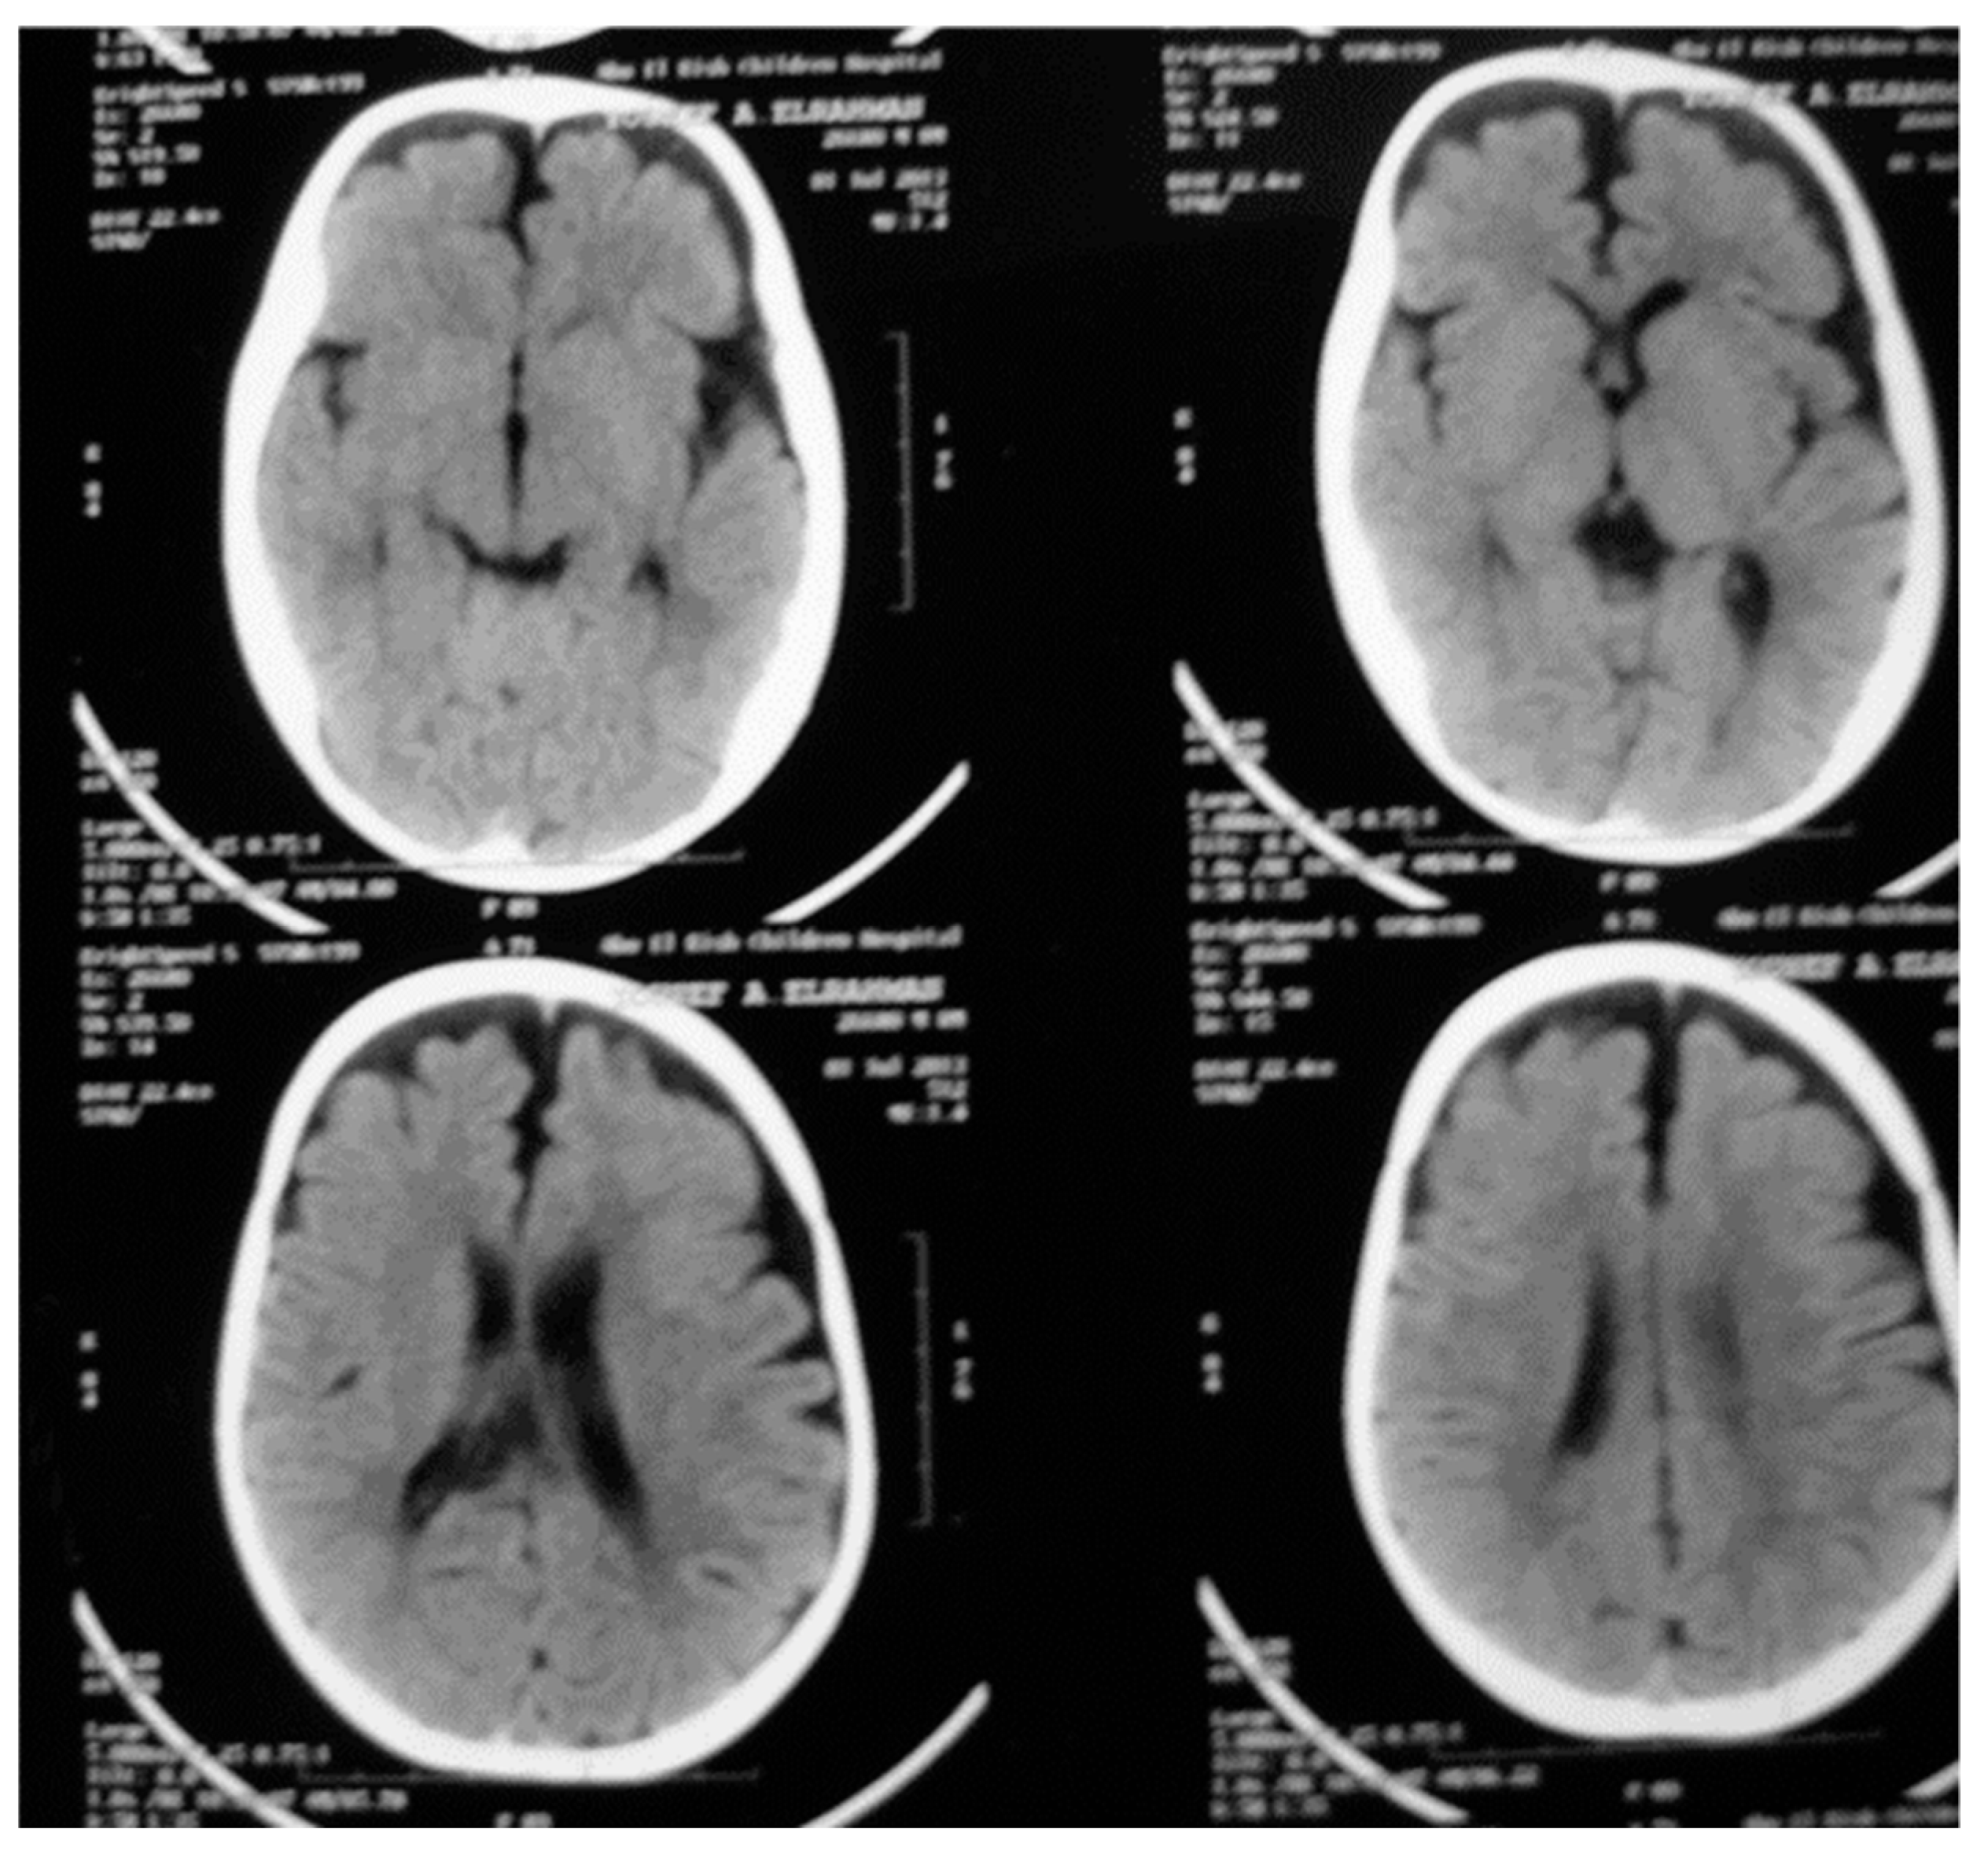

3.2. Radiologic Results